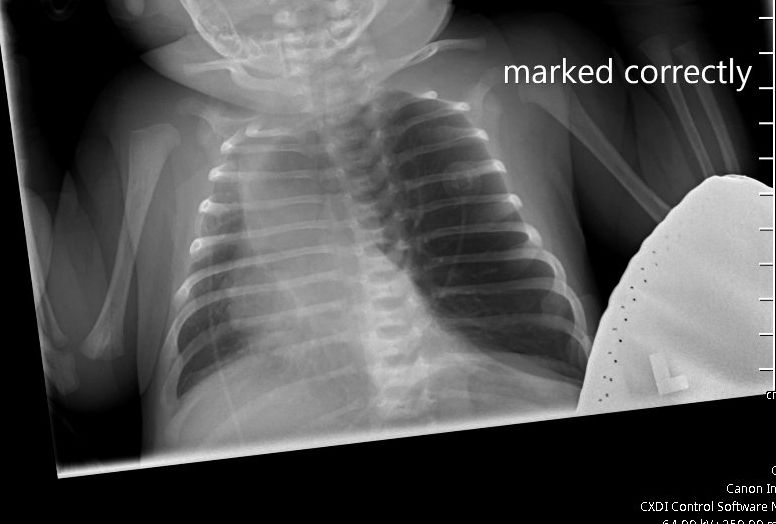

An 18-day-old female presented to the ED with concerns of apnea, cyanosis, and decreased feeding. The mother reported intermittent cyanosis of the lips, pale-appearing skin, and suspected apnea episodes. Since birth, Mom states patients had retractions since birth, which the PCP reassured her was normal periodic breathing. She had nasal flaring and grunting a couple of days after discharge from the nursery. Mom has noticed she breathes quickly, in the 60s or 70s at times.

Initial vitals in the ED showed hypoxemia, tachypnea, and fluctuating oxygen saturations were between 65-100% on room air. A chest X-ray is shown (Figure 1).